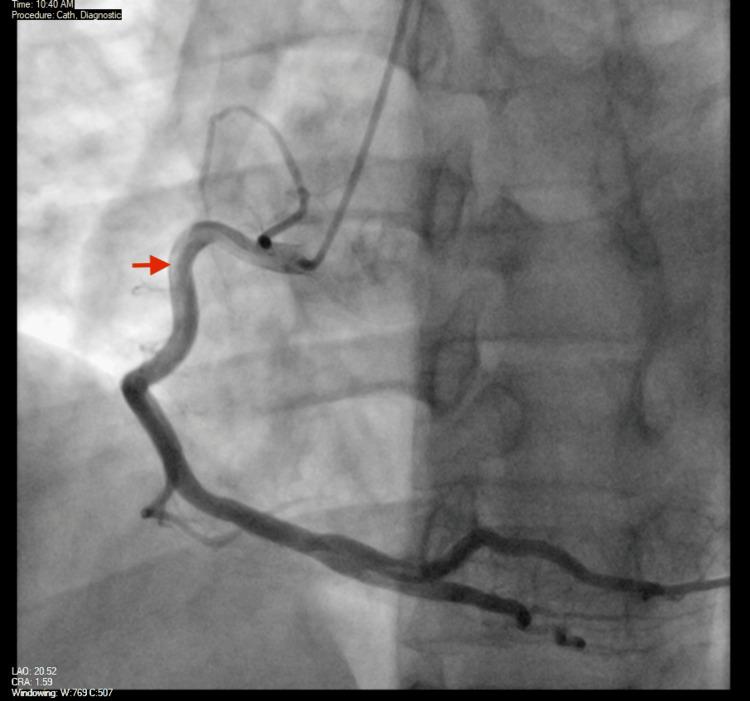

Kounis syndrome (KS) is an underrecognized and critical condition of acute coronary syndrome (ACS) triggered by an allergic reaction, via histamine-mediated coronary vasospasm and plaque disruption. We present a case of type 1 KS in a 42-year-old male patient who developed ST elevation myocardial infarction following an allergic reaction to epinephrine, diphenhydramine, and cocaine. Initially stable, he later experienced worsening chest pain with a significant rise in troponin. Coronary angiography with intravascular ultrasound (IVUS) imaging revealed a layered left anterior descending (LAD) thrombus with possible acute plaque rupture but no significant coronary artery disease (CAD) otherwise, which was successfully managed with medical therapy. This case underscores the importance of early recognition, cardiology involvement, and balancing treatment geared toward allergic and cardiac manifestations. This report aims to raise awareness of KS, and its documented exposures are essential for timely diagnosis, targeted management, and improved patient outcomes, as there would be more focus on treating the allergic reaction in these cases, which might be overlooked if ACS was to be attributed to CAD as the reason.

库尼斯综合征(KS)是一种由过敏反应引发的急性冠状动脉综合征(ACS),常因组胺介导的冠状动脉痉挛和斑块破裂而未被充分认识且病情危急。我们报告一例1型KS病例,患者为42岁男性,在对肾上腺素、苯海拉明和可卡因发生过敏反应后出现ST段抬高型心肌梗死。起初病情稳定,随后他胸痛加重,肌钙蛋白显著升高。冠状动脉造影及血管内超声(IVUS)成像显示左前降支(LAD)有分层血栓,可能存在急性斑块破裂,但无其他明显冠状动脉疾病(CAD),通过药物治疗成功处理。该病例强调了早期识别、心脏病学介入以及平衡针对过敏和心脏表现的治疗的重要性。本报告旨在提高对KS的认识,其记录的暴露情况对于及时诊断、针对性管理和改善患者预后至关重要,因为在这些病例中更多地关注治疗过敏反应,若将ACS归因于CAD作为原因,可能会忽略这一点。